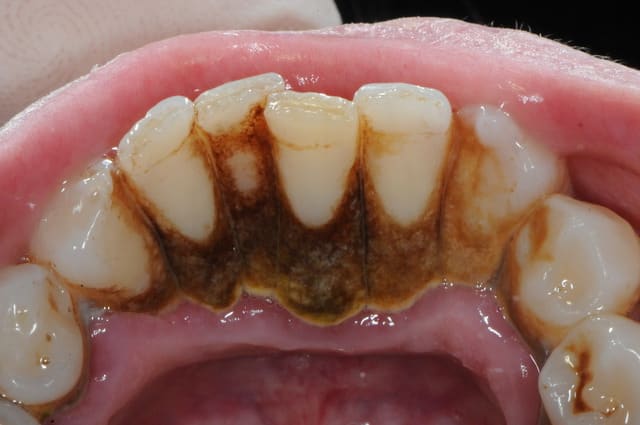

Vu cette semaine, en 2 jours,

3 cas d'allergie à la brosse à dents...